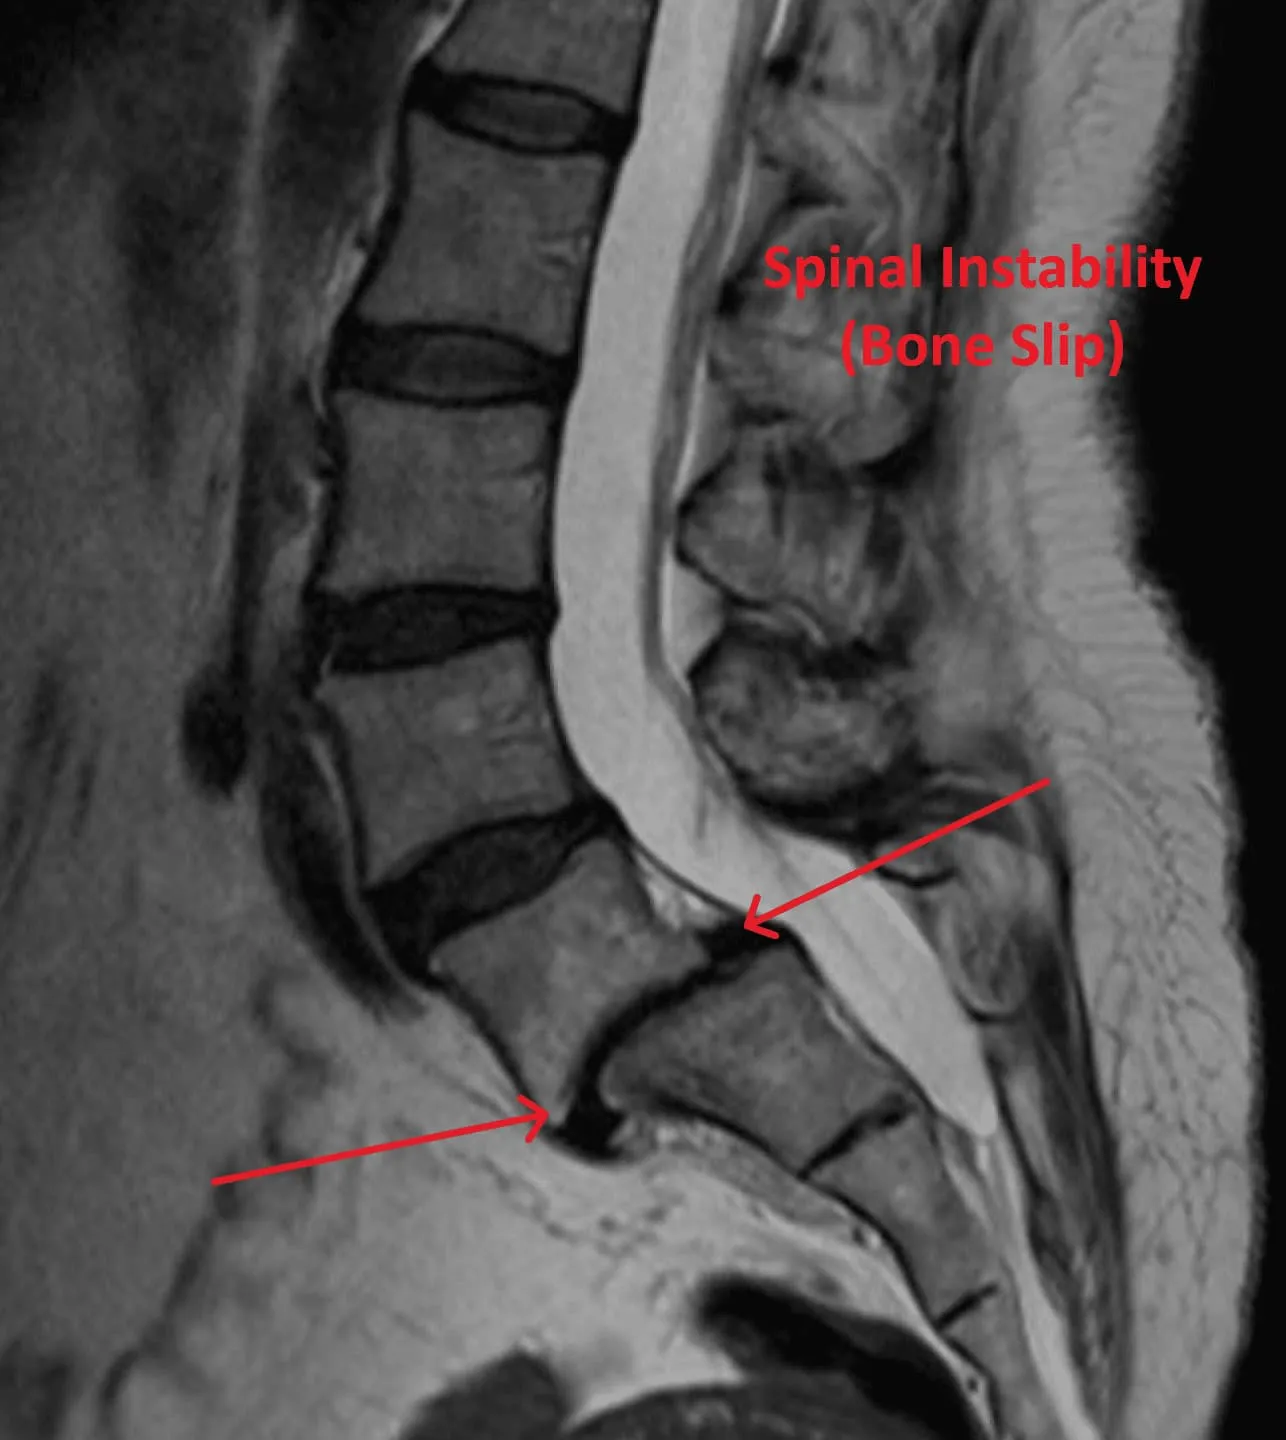

Spinal Instability

Untreated Root Cause

Stenosis Recurrence